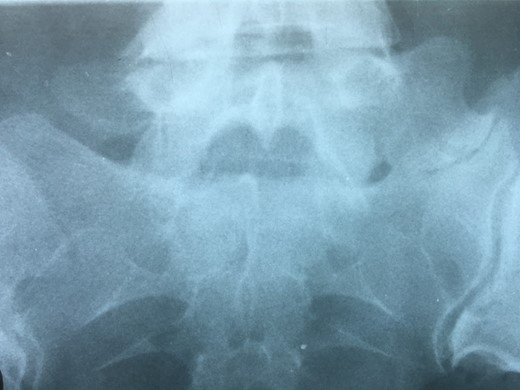

Degenerative changes at the facets and disc in the adjacent segment.

The partial fusion at the lower part of the lumbosacral transition produces important alterations in normal biomechanics at the levels immediately above and below the LSTV. Changes such as hypermobility and abnormal torque moments are present at the level above the LSTV, predisposing it to early degeneration (early disc pathology and facet joint degenerative disease). Restricted movement below the LSTV produces a protective effect against degeneration of disc and facets and is related to changes (facets are smaller and coronally oriented) in the dimensions of the lower level facet joints [7]. These alterations can be verified in the adjacent levels of the LSTV in our patient.